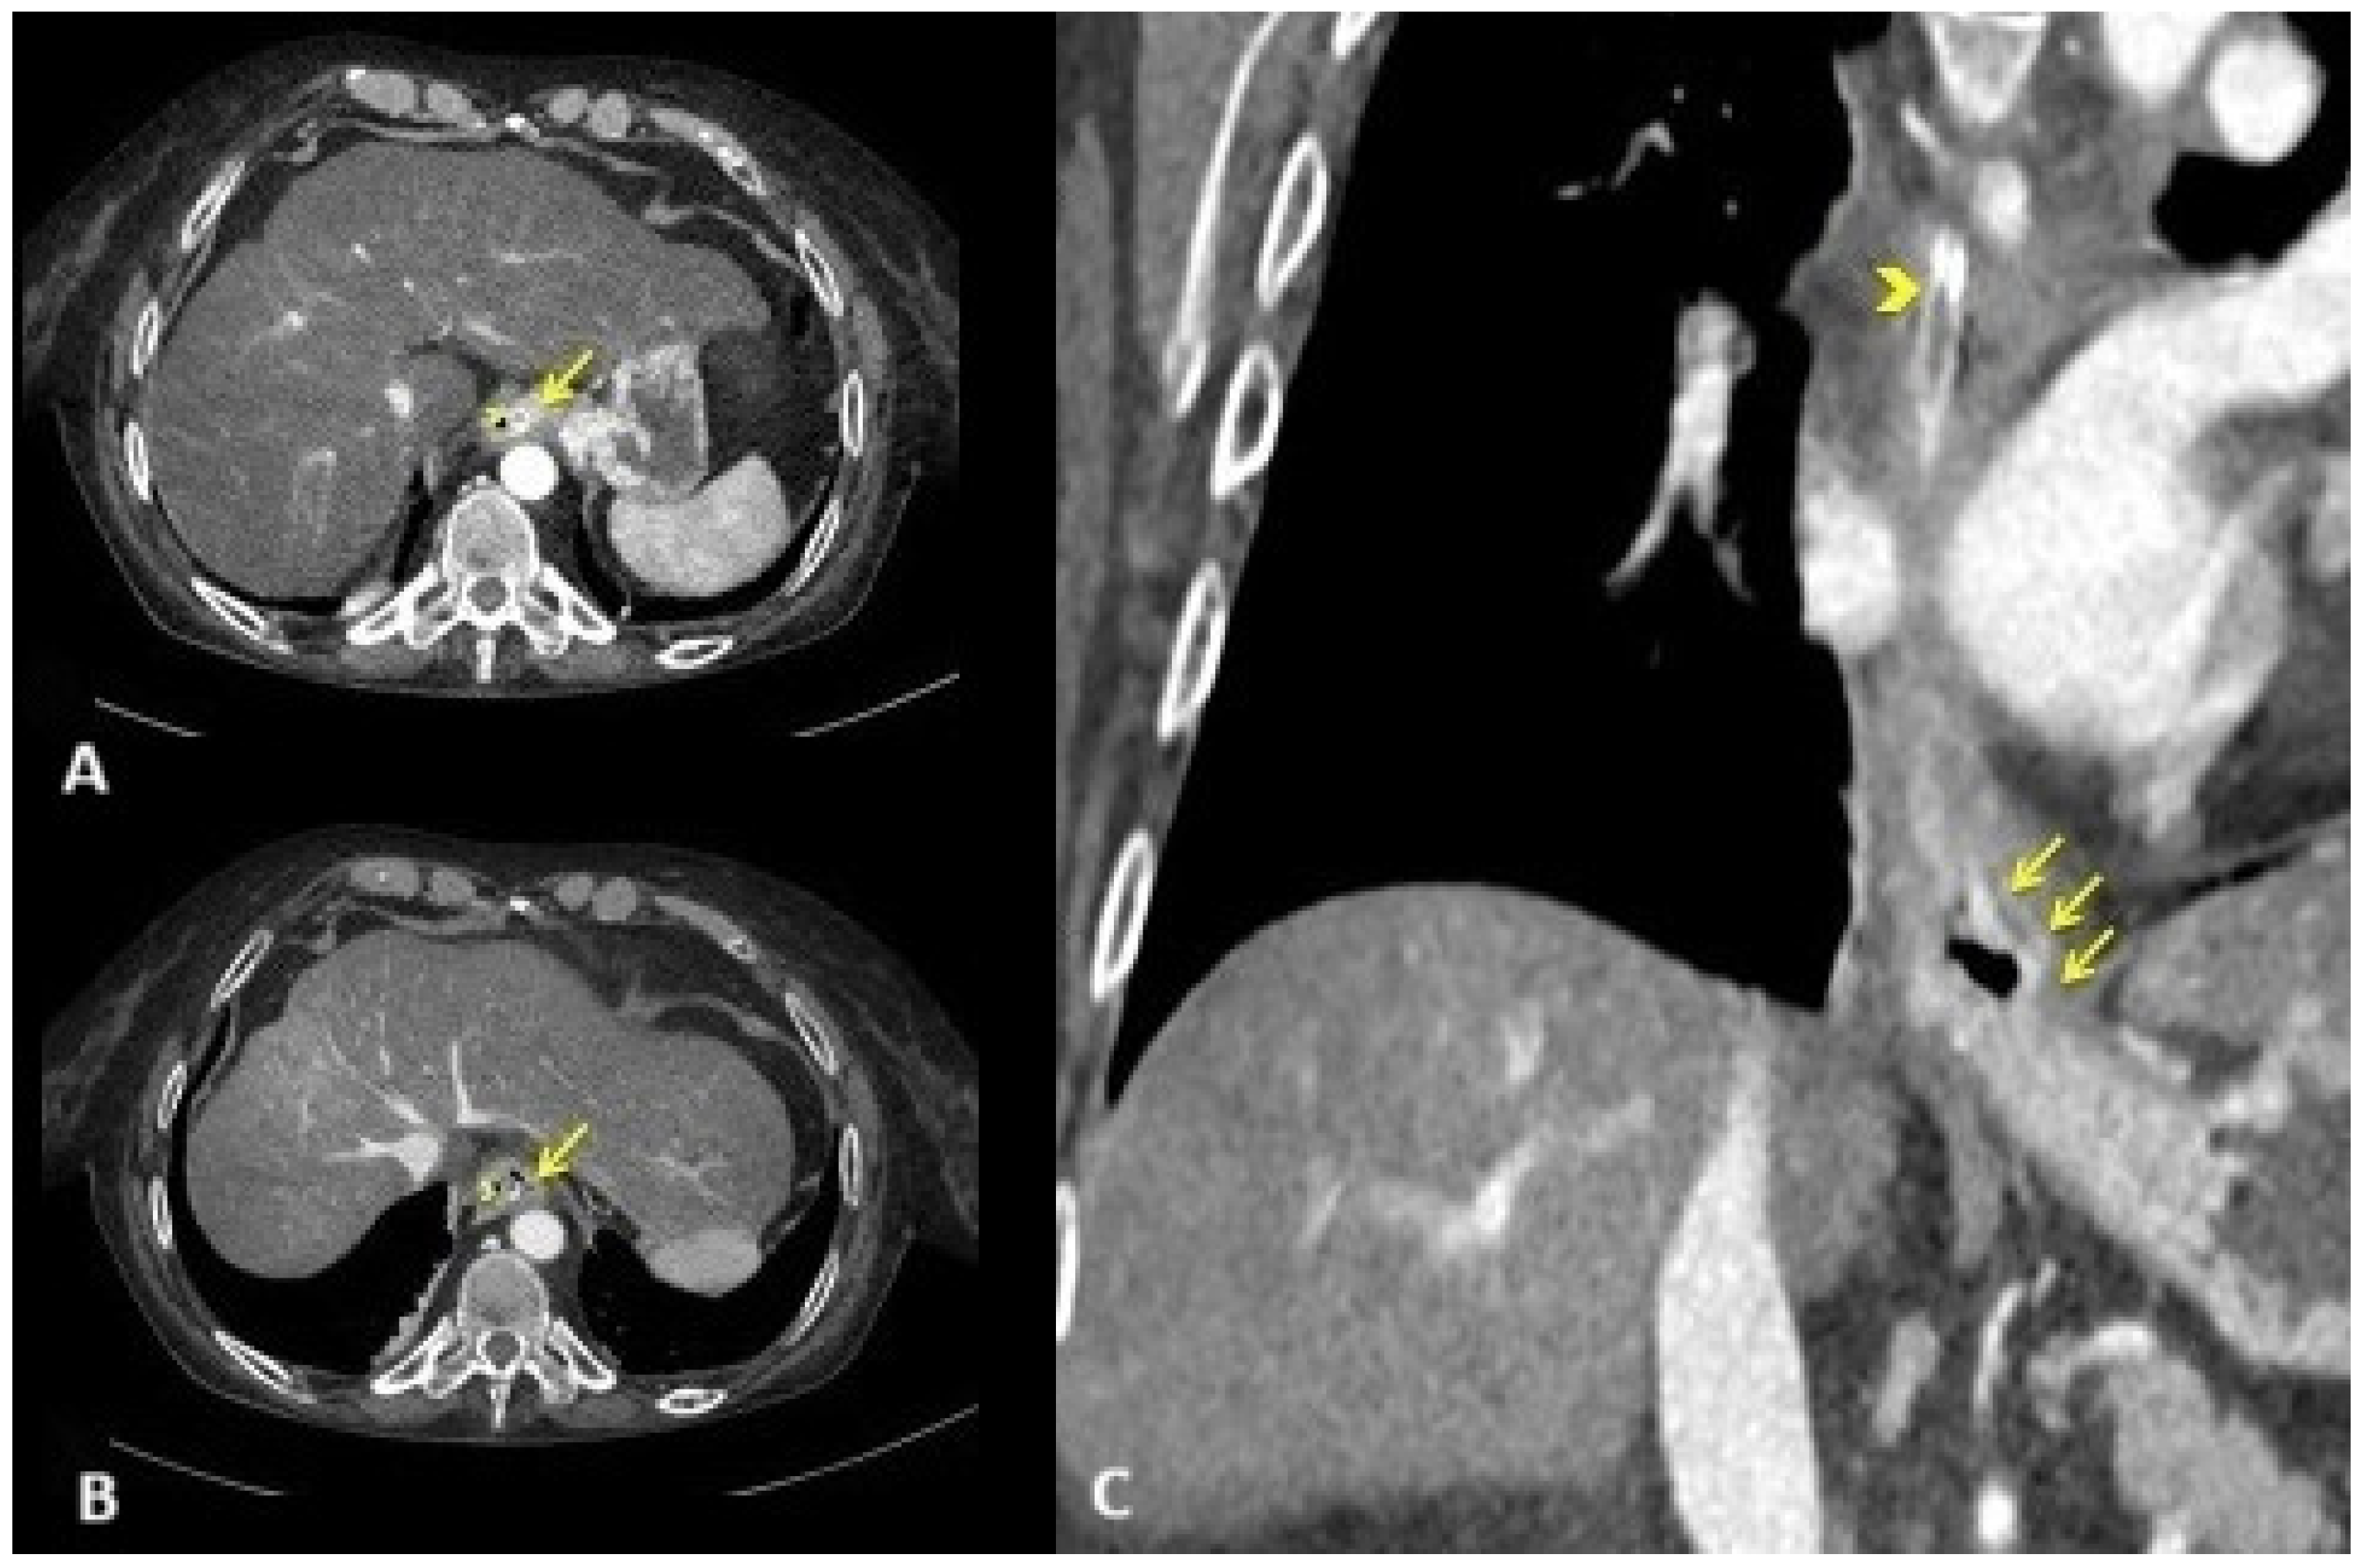

2.1. Diagnostic Evaluation